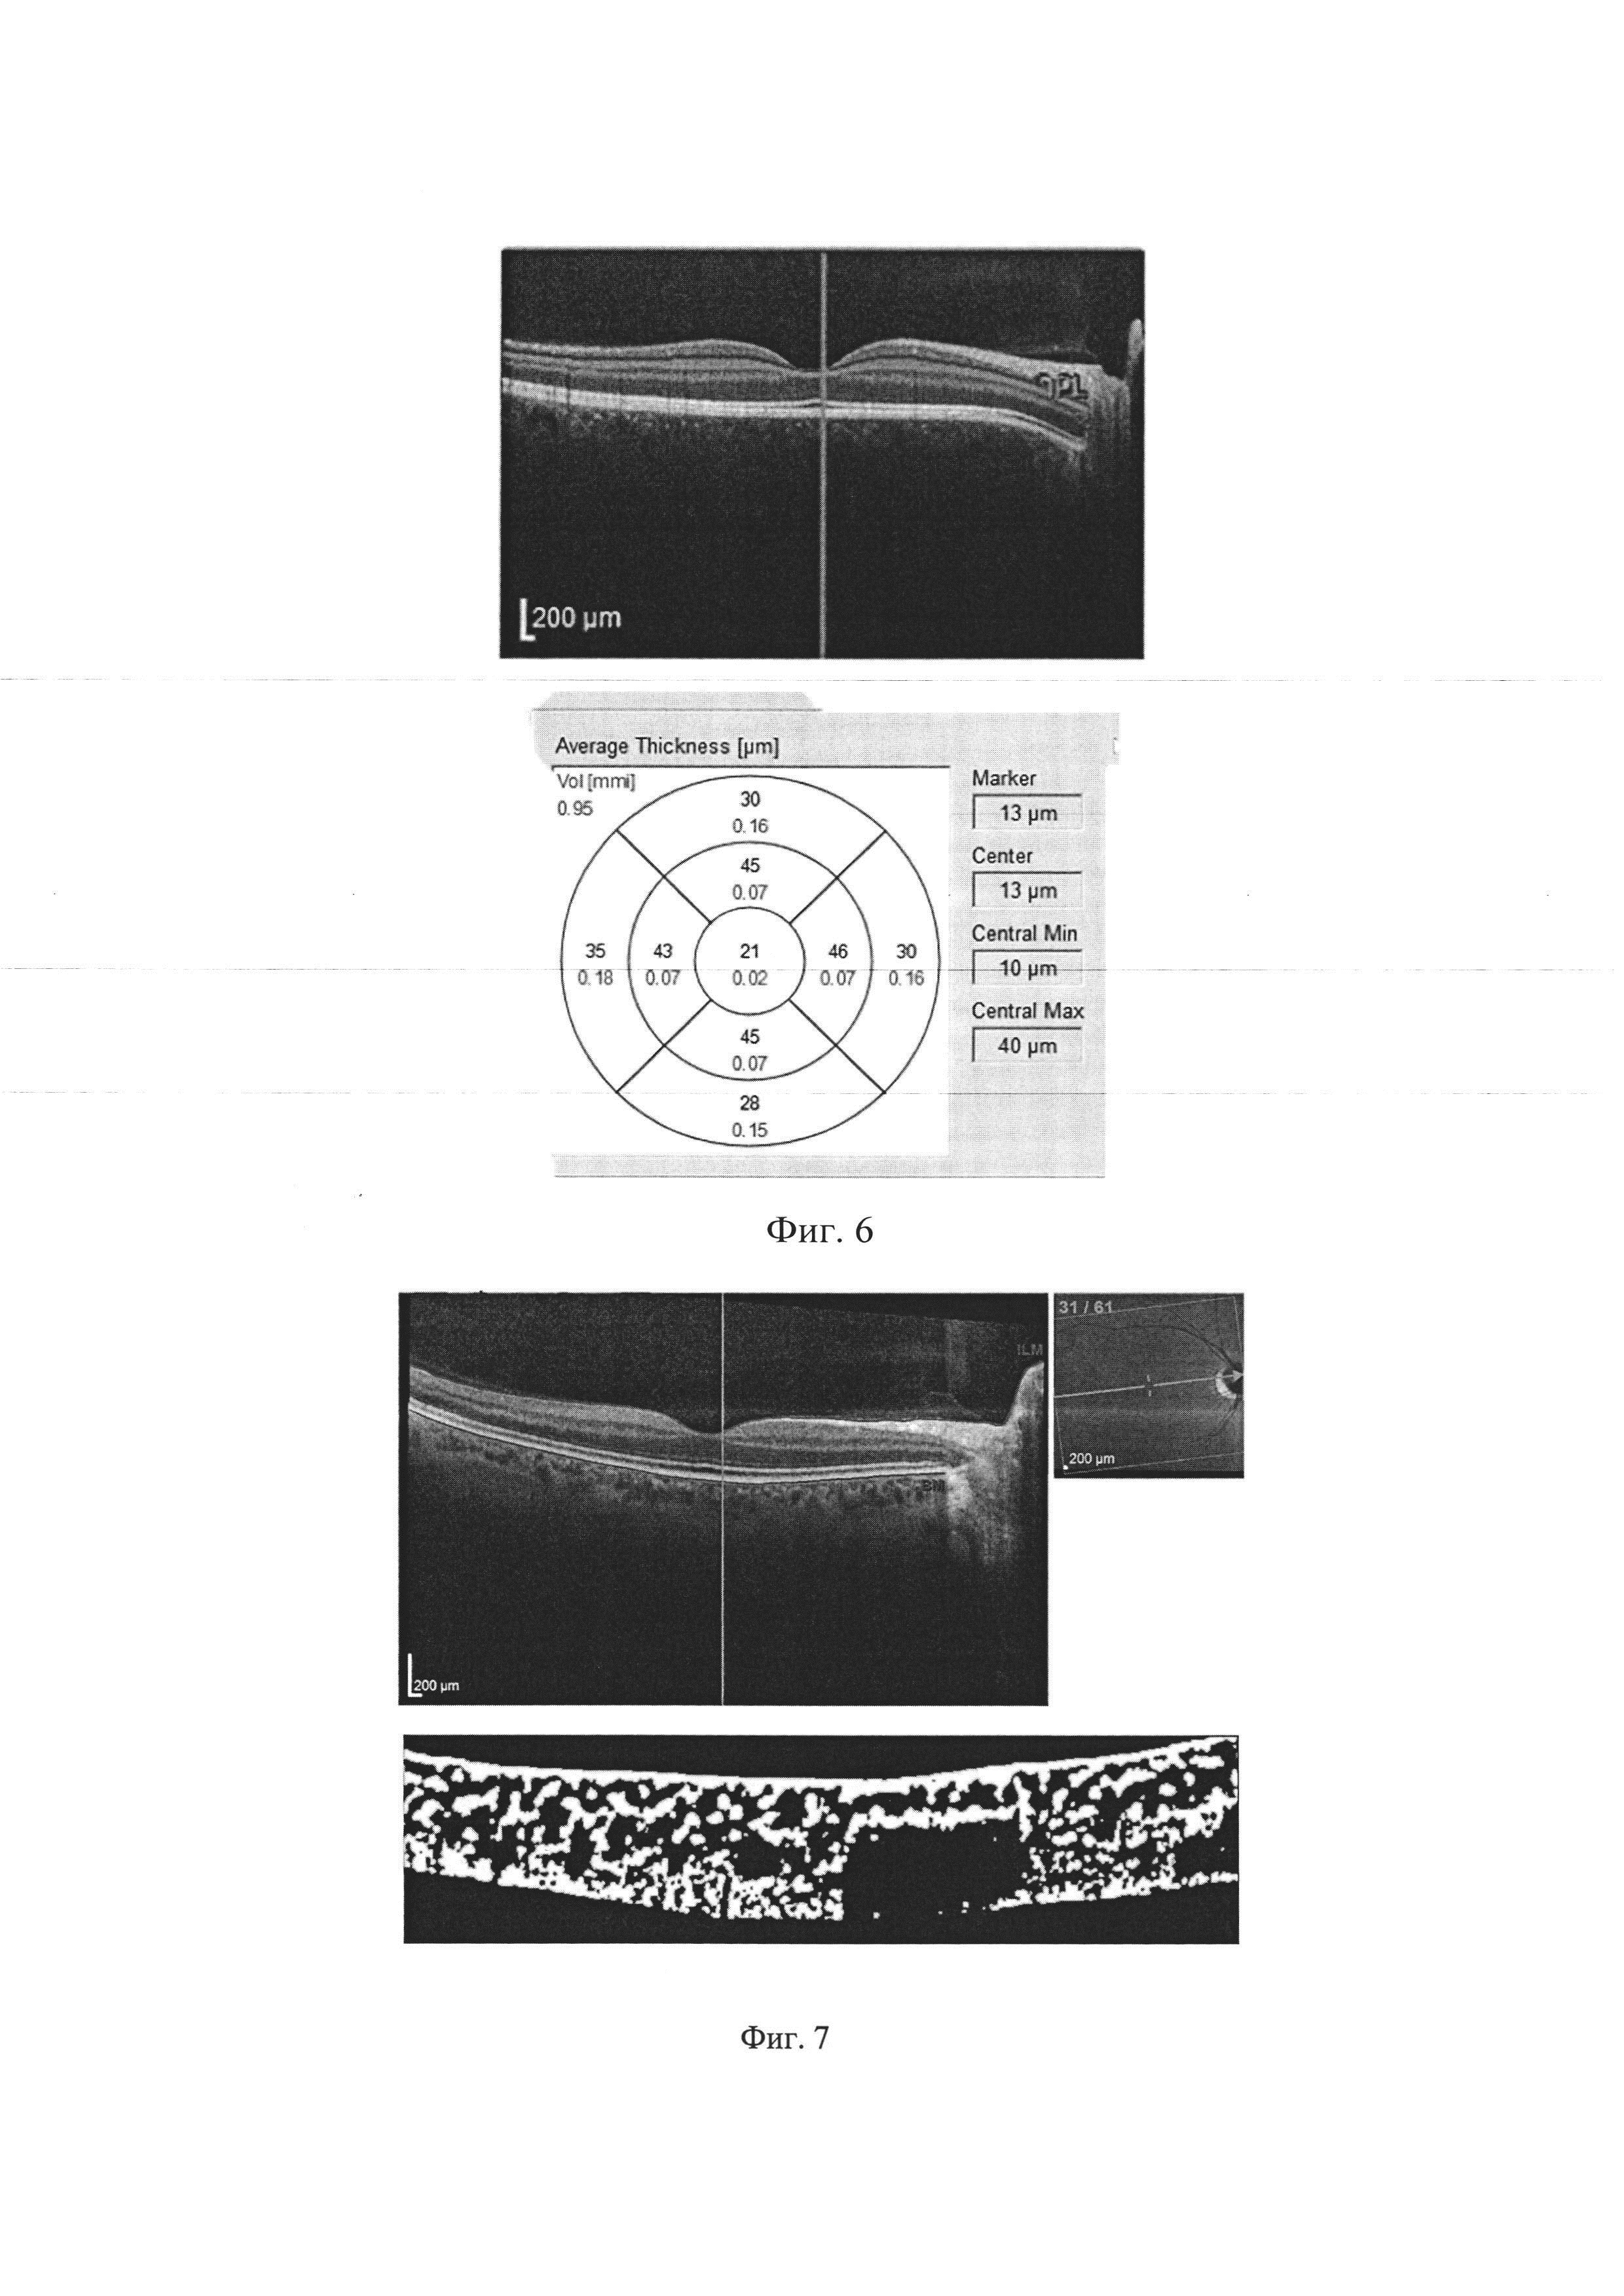

Изобретение относится к медицине, а именно к офтальмологии и неврологии, и предназначено для диагностики рассеянного склероза. Рассеянный склероз (PC) является одной из социально значимых проблем во всем мире. Это тяжелое, хроническое, демиелинизирующее заболевание центральной нервной системы, которое является причиной инвалидизации трудоспособных и социально активных молодых людей. Данное заболевание оказывает огромное влияние на полноценность почти всех категорий жизнедеятельности человека, таких как передвижение, самообслуживание, ориентация в пространстве и общение. Внимание офтальмологов к проблеме диагностики рассеянного склероза обусловлено высокой частотой выявления этого заболевания (от 45% до 80% случаев, по данным различных авторов). Особый интерес представляет тот факт, что оптическая нейропатия, как исход ретробульбарного неврита нередко является клинически изолированным синдромом рассеянного склероза - то есть самой ранней стадией заболевания, при которой уже имеются нейродегенеративные изменения. При длительности рассеянного склероза более 5 лет поражение зрительного анализатора выявляется у 70% больных. Аксоны ганглиозных клеток сетчатки имеют значительную протяженность и оканчиваются синаптическими контактами с ганглиозными клетками наружного коленчатого тела. Длина аксона ганглиозной клетки сетчатки около 75 мм. Аксоны последовательно проходят в трех анатомических структурах: зрительном нерве, хиазме и зрительном тракте. При воспалительном процессе в пучках аксонов или нахождении бляшки рассеянного склероза в зоне прохождения этих аксонов вокруг аксона возникает воспалительный отек и нарушается целостность его миелиновой оболочки. Это приводит к нарушению прохождениянервного импульса (потенциала) по аксону, в результате чего нарушаются зрительные функции. Для рассеянного склероза характерно ремиттирующее течение болезни - сочетание периодов обострения воспалительного процесса со стадиями ослабления воспаления (ремиссией). Быстрое снижение зрения при рассеянном склерозе в период обострения можно объяснить тем, что нарушение зрительных функций связано с преходящим отеком, нарушением миелинового покрытия аксона, а также угнетением функции окружающих аксон олигодендроцитов и астроцитов. Последующее улучшение зрительных функций связано со сравнительно быстрым рассасыванием отека и улучшением функциональных особенностей олигодендроцитов по выработке миелиновых композиций для восполнения образовавшихся дефектов миелинового покрытия аксона. Такое течение заболевания является характерным дифференциально-диагностическим признаком самой распространенной ремитирующей формы рассеянного склероза. Молекулярный субстрат для ремиссий появляется за счет восстановления демиелинизированной оболочки аксона между перехватами Ранвье, которая приобретает большую плотность натриевых каналов. В связи с этим аксон продолжает проводить потенциал, несмотря на малое количество миелина в зоне поражения. Применяя конфокальную микроскопию и реконструируя трехмерное компьютерное изображение, В. D. Тгарр и соавт. показали наличие повреждающих субстанций, воздействующих на аксоны и их миелиновую оболочку головного мозга больных рассеянным склерозом. При использовании антител к нефосфорилированным нервным волокнам (маркеры для участков нервной ткани с недостатком миелина) в стадии активного процесса при рассеянном склерозе было обнаружено обилие воспалительных клеток. Для сохранения аксона и модуляции нейротрансмиттеров имеют значение ионные каналы и ионные обменники. Нарушение этого процесса лежит в основе повреждений аксона. Целостность и функция аксона после его повреждения могут быть сохранены посредством применения нейропротекторов, которые блокируют или модулируют ионные потоки. В зоне поражения аксонов также определяются воспалительный отек, дегенерация и деструкция клеток нейроглии. В воспалительном инфильтрате определяются различные клеточные элементы: лимфоциты, нейтрофилы, макрофаги. В последующем эти клетки входят в состав бляшек рассеянного склероза. При непрогрессирующей форме рассеянного склероза характерно вялое течение воспалительного процесса в очаге поражения. В связи с этим, при неблагоприятном течении рассеянного склероза, выражающемся в длительном снижении зрительных функций, можно выделить 4 последовательные стадий разрушения аксонов, а именно: стадия дистрофии, стадия деструкции, стадия дегенерации на участке демиелинизации аксона. Последняя стадия - атрофия аксона, полностью прерывающая проведение нервного импульса от ганглиозной клетки сетчатки. По всей длине аксона ганглиозной клетки сетчатки, на любом участке от решетчатой пластинки склеры до наружного коленчатого тела, нарушение трофики и целостности миелиновой оболочки является началом патологического процесса в аксоне. В последующем этот процесс с миелиновой оболочки переходит на нервное волокно, что и приводит к нарушению зрительных функций. В наружном коленчатом теле аксоны ганглиозных клеток сетчатки через синаптические связи передают нервный импульс (потенциал) ганглиозным клеткам наружного коленчатого тела. Аксоны ганглиозных клеток наружного коленчатого тела также имеют значительную длину, доходя до корковых структур затылочных отделов головного мозга. Ониобразуют зрительную лучистость Грациоле и оканчиваются синаптическими связями в корковых структурах зрительных областей головного мозга. При поражении рассеянным склерозом отдельных зон этого участка зрительного пути также возникают нарушение проведения нервного импульса и нарушение зрительных функций. При нахождении очага поражения в зрительном нерве снижаются зрительные функции только больного глаза. При поражении зрительного пути в хиазме, зрительном тракте, коленчатом теле и зрительной лучистости Грациоле страдают зрительные функции обоих глаз. Так, немало работ проведено и проводится именно в этом направлении. Пациентам проводят комплексное нейроофтальмологическое обследование, включающее сбор анамнеза и традиционные функциональные и объективные методы диагностики: визометрию, рефрактометрию, кинетическаю периметрию на белый объект и цвета (красный и зеленый), биомикроскопию, офтальмоскопию (Захаров А.В. и др., Оценка рисков трансформации монофокального клинически изолированного синдрома в клинически достоверный рассеянный склероз, Журнал неврологии и психиатрии им. Корсакова, Т. 113, №2, Выпуск 2, 2013 г., с. 28-32; Малов В.М. и др., Новые перспективы ранней диагностики оптического неврита и рассеянного склероза, Неврологический вестник, журнал имени В.М. Бехтерева, Том XLII, №1, 2010 г., с. 72-74), однако результаты данных исследований не могут однозначно свидетельствовать за точность диагноза. Перспективным является направление исследования области зрительного нерва с помощью оптической когерентной томографии, поскольку объективизация и достаточно четкая визуализация получаемых на сканах структур может более достоверно свидетельствовать о развитии заболевания. Так, на уровни техники известен способ диагностики рассеянного склероза (Синеок Е.В. и др., Ранняя диагностика нейродегенеративных изменений при рассеянном склерозе на основе программы диагностики сетчатки, Журнал международной медицины, 2015 г., №2(13), с. 127-130), принятый нами за прототип. Способ заключается в проведении комплексного нейроофтальмологического обследования, включающего оптическую когерентную томографию перипапиллярной области диска зрительного нерва и макулярной области сетчатки на обоих глазах. Кроме того, всем пациентам проводилась оптическая когерентная томография диска зрительного нерва и перипапиллярных нервных волокон сетчатки. Однако, данный способ обладает следующими недостатками. Оценка только параметров сетчатки может привести как к ложноположительным, так и к ложноотрицательным результатам, поскольку данные параметры в целом не позволят провести высокоточную диагностику именно рассеянного склероза. Таким образом, существует потребность в способе диагностики рассеянного склероза, лишенном вышеуказанных недостатков. Техническим результатом настоящего изобретения является повышение точности и достоверности диагностики рассеянного склероза за счет оценки высокочувствительного и специфичного маркера, такого как параметры хориоидеи, обработанные с помощью математической модели. Этот технический результат достигается тем, что в способе диагностики рассеянного склероза, включающем оптическую когерентную томографию перипапиллярной области диска зрительного нерва и макулярной области сетчатки обоих глаз в рамках комплексного нейроофтальмологического обследования, предлагается выбирать компьютерное изображение хориоидеи, проходящее через фовеолу, в центральной части изображения хориоидеи выделяют участок шириной 1500 мкм, центрированном относительно положения фовеолы; осуществляют предварительную обработку изображения с помощью компьютерной программы количественной обработки состояния сосудов хориоидеи на компьютерных изображениях оптической когерентной томографии глазного дна; на ранее указанном участке определяют толщину хориоидеи в макулярной области (choroidal thickness - СТ), а также удельную долю просветов кровеносных сосудов от общей площади, занимаемой хориоидеей на изображении (proportion of blood vessel lumens in the choroid - PBVLC), после чего вносят полученные значения в формулу где Р - хориоидальный показатель рассеянного склероза, и при значении Р>0,575 хотя бы на одном глазу диагностируют рассеянный склероз. На фиг. 1-2 показаны моменты центровки скана и его обработки в компьютерной программе. На фиг. 3-8 показаны иллюстрации к клиническим примерам. Способ осуществляют следующим образом. В рамках проведения комплексного нейроофтальмологического обследования проводят оптическую когерентную томографию заднего сегмента глаза перипапиллярной области диска зрительного нерва и макулярной области сетчатки (мы проводили исследование с помощью оптического когерентного томографа Spectralis OCT BluePeak (Heidelberg Engineering, Германия)). После этого выбирают компьютерное изображение хориоидеи, проходящее через фовеолу, осуществляют его предварительную обработку в «Программе количественной обработки состояния сосудов хориоидеи на компьютерных изображениях оптической когерентной томографии глазного дна» (свидетельство о гос. регистрации программ для ЭВМ №2017611818 от 09 февраля 2017 г.) Перед обработкой проводят центровку изображения хориоидеи относительно положения фовеолы, для исследования выделяют участок шириной 1500 мкм (Фиг. 1). После обработки (Фиг. 2) определяют с помощью программы толщину хориоидеи в макулярной области СТ (choroidal thickness), а также удельную долю просветов кровеносных сосудов от общей площади, занимаемой хориоидеей на скане PBVLC (proportion of blood vessel lumens in the choroid). Уменьшение толщины хориоидеи и увеличение удельной доли просвета кровеносных сосудов от общей площади хориоидеи вследствие атрофии паренхимы свидетельствует об изменении кровообращения хориоидального тракта при демиелинизирующих заболеваниях. Полученные значения вносят в формулу где Р - хориоидальный показатель рассеянного склероза. Такой подход дал возможность увеличить прогностическую значимость показателей толщины хориоидеи и удельной доли просветов кровеносных сосудов, так как при использовании обоих показателей в вышеуказанной математической модели, значения чувствительности и специфичности для показателя Р составили 94,6% и 90,3% соответственно, в сравнении со считавшимися ранее максимально чувствительными и специфичными показателями морфометрии сетчатки (см. Таблицу 1). Таким образом, в данном способе диагностики рассеянного склероза важен анализ показателей состояния хориоидеи. Пример 1. Пациентка В., 34 лет, поступила в неврологическое отделение МОНИКИ с жалобами на снижение чувствительности в области правого предплечья и контрастности зрения правого глаза. Пациентке было назначено дополнительное обследование, в которое входило МРТ головного мозга с контрастированием и осмотр офтальмолога. На офтальмологическом осмотре острота зрения составила 1,0 на обоих глазах. ВГД OU- 16 мм рт ст. Биомикроскопия и офтальмоскопия не выявили изменений со стороны переднего и заднего отделов глаза. По результатам компьютерной периметрии не обнаружено скотом, сужения полей зрения или снижения светочувствительности на правом глазу. При проведении оптической когерентной томографии на правом глазу зафиксировано снижение толщины перипапиллярных нервных волокон в височном квадранте до 55 мкм. А также изменения общего макулярного объема, который составил 7,59 мкм3, уменьшение объема внутренних слоев сетчатки: объем ганглиозного слоя - 0,82 мкм3 и внутреннего плексиформного слоя сетчатки - 0,71 мкм3 (Фиг. 3). Для диагностики по предлагаемому способу рассчитали показатель Р. Для этого с помощью программы (Фиг. 4) были измерены толщина хориоидеи СТ (221,08 мкм) и удельная доля просветов кровеносных сосудов PBVLC (0,585), показатель Р на правом глазу составил 0,768. Для левого глаза (Фиг. 5) данные соответственно составили СТ (220,28 мкм), PBVLC (0,633), показатель Р на левом глазу составил 0,997. Согласно полученным показателям, у пациента диагностирован рассеянный склероз предлагаемым способом. Через неделю, после проведения МРТ с контрастированием, данный диагноз был подтвержден: Мр-картина многоочагового поражения белого вещества головного мозга с наличием супратенториальных очагов и вовлечением в процесс мозолистого тела, без признаков активности (нарушения ГЭБ), по критериям диагностики соответствует рассеянному склерозу. Таким образом, установлен диагноз: рассеянный склероз, ремитирующего течения, назначена соответствующая терапия. Пример 2. Пациентка А, 25 лет, поступила в офтальмологическое отделение МОНИКИ с жалобами на частые головные боли, периодические боли в области правого глаза и сужение полей зрения, а также боли в спине и правом предплечье. Для постановки диагноза было назначено МРТ с контрастом, консультация офтальмолога. На момент осмотра жалоб со стороны органа зрения пациента не предъявляла, острота зрения составила 1,0 на обоих глазах, ВГД на по Маклакову OU- 18 мм. рт.ст. С помощью биомикроскопии и офтальмоскопии не удалось выявить изменений со стороны органа зрения. По данным ОКТ изменений со стороны зрительного нерва (толщины перипапиллярных нервных волокон в височном квадранте - 73 мкм), сетчатки (объем ганглиозного слоя - 1,95 мкм3 и внутреннего плексиформного слоя сетчатки - 0,95 мкм3). (Фиг. 6). Для диагностики по предлагаемому способу рассчитали показатель Р. Для этого с помощью программы (Фиг. 7) были измерены толщина хориоидеи СТ (438,85 мкм) и удельная доля просветов кровеносных сосудов PBVLC (0,626), показатель Р на левом глазу составил 0,012. Для правого глаза (Фиг. 8) данные соответственно составили СТ (452,26 мкм), PBVLC (0,617), показатель Р на левом глазу составил 0,006. Заключение МРТ: MP-признаков патологических изменений головного мозга не выявлено. С диагнозом идиопатическая головная боль (мигрень с аурой) и назначена терапия. С помощью предлагаемого способа было обследовано 68 пациентов с диагнозом рассеянный склероз с ремиттирующим течением, из них 43 женщины (63%) и 25 мужчин (34%), в среднем возраст мужчин составил 34,9 года, женщин - 33,7. Статистически значимые различия по описанным показателям между мужчинами и женщинами в выборке пациентов не обнаружено. Для сравнения была взята контрольная группа из 23 здоровых лиц с отсутствием офтальмологической патологии после комплексного обследования (визометрия, тонометрия, пахиметрия, компьютерная периметрия, офтальмоскопия, оптическая когерентная томография). Всем пациентам была проведена МРТ с контрастированием. В результате данного исследования была доказана высокая чувствительность и специфичность показателей хориоидеи, обработанных с помощью математической модели, для диагностики рассеянного склероза. Таким образом, предлагаемый способ позволяет повысить точность и достоверность диагностики рассеянного склероза за счет высокочувствительного и специфичного параметра, такого как оценка хориоидеи, а именно ее параметров, обработанных с помощью математической модели.